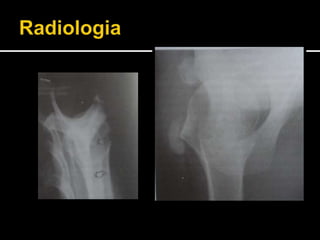

 Incidências:

 AP verd : tendão do SE

 AP com RI: tendão do IE e Rm

 AP com RE: tendão do Subescapular

 Axilar

 Perfil da escápula.

 TC e RNM: podem auxiliar no diagnóstico (?)

 2 tipos de aparência radiológica:

 Tipo 1: na fase aguda ou reabsorvida, em que não há

delimitação precisa das bordas do depósito.

 Tipo 2: na fase subaguda ou crônica, em que ocorre

homogeneidade na densidade do depósito e as bordas são

bem delimitadas.

 O depósitode cálcio ocorre dentro de um dos tendões do manguito rotador. (principalmente do músculo supra-espinal).  Incidências:  AP verd : tendão do SE  AP com RI: tendão do IE e Rm  AP com RE: tendão do Subescapular  Axilar  Perfil da escápula.

 TC eRNM: podem auxiliar no diagnóstico (?)  2 tipos de aparência radiológica:  Tipo 1: na fase aguda ou reabsorvida, em que não há delimitação precisa das bordas do depósito.  Tipo 2: na fase subaguda ou crônica, em que ocorre homogeneidade na densidade do depósito e as bordas são bem delimitadas.